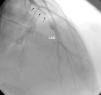

ResultsEleven patients who presented with ACS and were diagnosed with MPNs were studied (nine men, two women, mean age 40.18±8.4 years). Six patients had no major CV risk factors; only one had two risk factors, while the rest had one. The patients’ mean age was 32.9±6 years when they first suffered MI. Case 1 also had concomitant jugular vein thrombosis, case 2 had portal vein thrombosis and case 11 had peripheral arterial thrombosis. Splenomegaly was seen in five patients and hepatosplenomegaly in two. Ten patients had anterior MI and one had inferior MI. In two patients (cases 2 and 4) MI was complicated by cardiac arrest. On coronary angiography, six patients had left anterior descending (LAD) lesions (Figure 1 and Supplementary Video 1 represent case 4), two patients had LAD and concomitant diagonal lesions, one patient had LAD and circumflex artery lesions, one patient had a right coronary artery lesion and one patient's angiography was normal. All lesions were thrombotic, causing total or sub-total occlusion, and coronary arteries other than the infarct-related arteries were normal. Nine patients underwent percutaneous coronary intervention and two patients underwent coronary artery bypass grafting due to dissection of the LAD (Table 1).